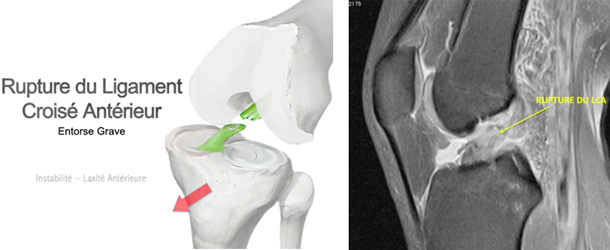

Rupture du ligament croisé antérieur

Le ligament croisé antérieur (LCA) est un ligament qui se situe au centre de l’articulation du genou dont le rôle est de stabiliser le genou à la fois d’avant en arrière et en rotation.

Lorsque le genou est soumis à une contrainte brutale en torsion, le LCA peut être étiré et se rompre. Cette situation est particulièrement fréquente dans la pratique du ski ou des sports dits « pivots » comme le football ou le handball.

L’absence de ligament croisé peut rendre le genou « instable » à différents degrés, ce qui peut nécessiter sa reconstruction chirurgicale. De plus, la « laxité » observée peut conduire à léser des structures anatomiques articulaires telles que les ménisques ou le cartilage, et donc à terme entraîner de l’arthrose.

Par la suite, c’est l’association d’un traumatisme du genou en torsion, de la sensation d’une instabilité, et de la mise en évidence d’une laxité à l’examen, qui signe la rupture du LCA.

Le diagnostic est alors complété par des radiographies et par une IRM qui permettent de visualiser la rupture, de mesurer la laxité et de rechercher des lésions associées méniscales, cartilagineuses ou ligamentaires.